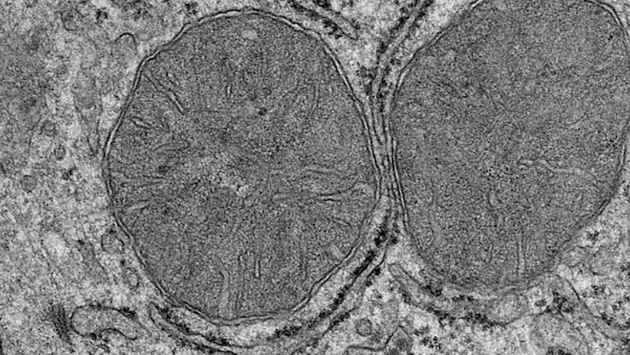

Ученые обнаружили, что вид и запах еды запускают фрагментацию митохондрий в клетках печени. Процесс начинается с РОМС-нейронов, которые активируют протеинкиназы. Исследование опубликовано в журнале Science.Когда наши органы чувств обнаруживают пищу, организм готовится к ее приему, вырабатывая слюну и желудочный сок. В новом исследовании ученые внимательно рассмотрели митохондрии в клетках печени, которые очень важны для метаболизма и выработки энергии.Ученые проводили опыты на мышах. Голодные животные могли только видеть еду и ощущать ее запах. Проанализировав состояние митохондрий в печени спустя всего несколько минут, ученые обнаружили, что в организмах мышей запустились процессы, обычно стимулируемые потреблением пищи. Исследователи обнаружили, что митохондрии клеток печени изменили свою форму и подготовили печень к метаболизму глюкозы — прохождению пути углеводами, содержащимся в пище, с момента, когда мы их употребляем, до момента, когда они достигают клеток.Такую реакцию запускают РОМС-нейроны, которые активируются условно рефлекторными стимулами — видом или запахом еды. Они могут всего за несколько секунд подать печени сигнал о том, что нужно приготовиться к приему пищи.РОМС-нейроны активируют протеинкиназы семейства B. Они запускают фосфорилирование (замещение любого атома или группы атомов на остаток фосфорсодержащей кислоты) в митохондриальный белок — фактор деления митохондрий (mitochondrial fission factor, MFF). Мутация, которая подавляет весь процесс фосфорилирования, нарушает и выработку глюкозы в печени. Этот процесс важен для регуляции активности белка и влияет на чувствительность печени к инсулину.Исследование показывает, насколько тесно связаны между собой сенсорное восприятие пищи, адаптивные процессы в митохондриях и чувствительность к инсулину, которая нарушается при сахарном диабете второго типа. Результаты могут помочь в его лечении.Автор: Екатерина Новикова.